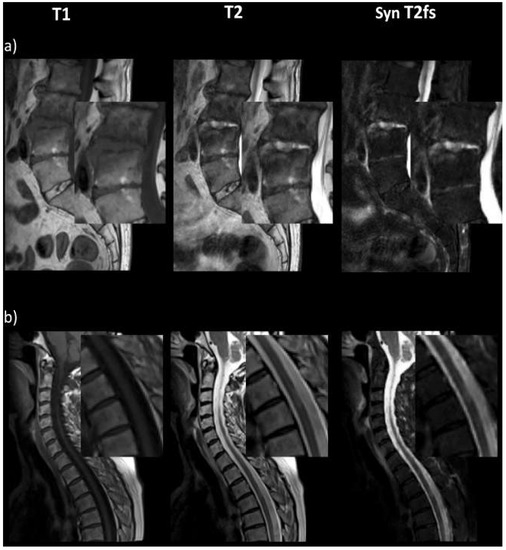

- Haubold, J.; Demircioglu, A.; Theysohn, J.M.; Wetter, A.; Radbruch, A.; Dörner, N.; Schlosser, T.W.; Deuschl, C.; Li, Y.; Nassenstein, K.; et al. Generating Virtual Short Tau Inversion Recovery (STIR) Images from T1- and T2-Weighted Images Using a Conditional Generative Adversarial Network in Spine Imaging. Diagnostics 2021, 11, 1542. [Google Scholar] [CrossRef]

- Finck, T.; Li, H.; Grundl, L.; Eichinger, P.; Bussas, M.; Mühlau, M.; Menze, B.; Wiestler, B. Deep-Learning Generated Synthetic Double Inversion Recovery Images Improve Multiple Sclerosis Lesion Detection. Investig. Radiol. 2020, 55, 318–323. [Google Scholar] [CrossRef]

- Finck, T.; Li, H.; Schlaeger, S.; Grundl, L.; Sollmann, N.; Bender, B.; Bürkle, E.; Zimmer, C.; Kirschke, J.; Menze, B.; et al. Uncertainty-Aware and Lesion-Specific Image Synthesis in Multiple Sclerosis Magnetic Resonance Imaging: A Multicentric Validation Study. Front. Neurosci. 2022, 16, 889808. [Google Scholar] [CrossRef] [PubMed]

- Kim, S.; Jang, H.; Jang, J.; Lee, Y.H.; Hwang, D. Deep-learned short tau inversion recovery imaging using multi-contrast MR images. Magn. Reson. Med. 2020, 84, 2994–3008. [Google Scholar] [CrossRef] [PubMed]